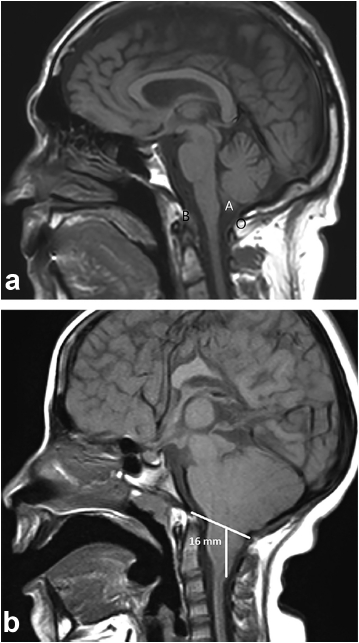

La ectopia de las amígdalas cerebelosas es considerada como el desplazamiento inferior de las mismas cuando es menor o igual a 5 mm.14,15

Un descenso mayor a 5 mm es considerado una variante de la malformación de Chiari.14,16

La RM es la modalidad de elección, prefiriéndose los cortes sagitales para la medición, ya que en los coronales se dificulta la visualización de los límites del agujero Magno.17

La medida debe tomarse trazando una línea recta entre el basión y el opistión del agujero Magno. Luego se traza una línea perpendicular a la primera, hasta el extremo distal de la amígdala herniada (►Fig. 3).

Existe disenso entre los estudios de cohorte en relación al valor exacto en milímetros del descenso amigdalar. La ►Tabla 1 resume las medidas del descenso amigdalar según el grupo etario.20

Existe relación entre el grado de descenso amigdalino y la presencia y grado de sintomatología,17 descensos menores a 10 mm suelen no dar síntomas.19